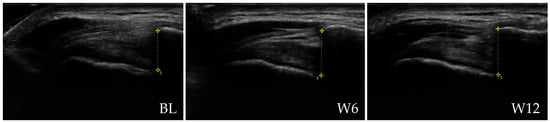

Figure 5 presents representative ultrasound images of the shoulder of a patient from the rESWT group at BL, W6 and W12, illustrating changes in AHD.

Representative ultrasound images of the shoulder of a patient from the rESWT group at baseline (BL), 6 weeks (W6) and 12 weeks (W12) post-baseline, illustrating AHD measurements indicated by vertical lines (10.3 mm at BL, 10.9 mm at W6 and 11.0 mm at W12). All patient-identifying information has been removed to protect privacy.